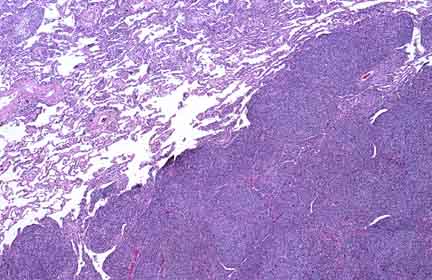

Grade 3 Follicular Lymphoma

An example of grade 3 follicular lymphoma, here in the lung. This is the least common of the 3 grades of follicle-forming lymphoma. The large cells are more "blastic" than small-cleaved ones, and thus they are the more likely to forget such sophisticated lymphoid behaviors as forming follicles.

A neoplastic follicle at medium power. Even though these are relatively high grade neoplastic lymphoid cells, note that the mitotic rate (as well as you can perceive it at this power) is lower than what would be seen in the ferociously mitotic normal germinal center.

The large cells predominate. Most of them are centroblasts.